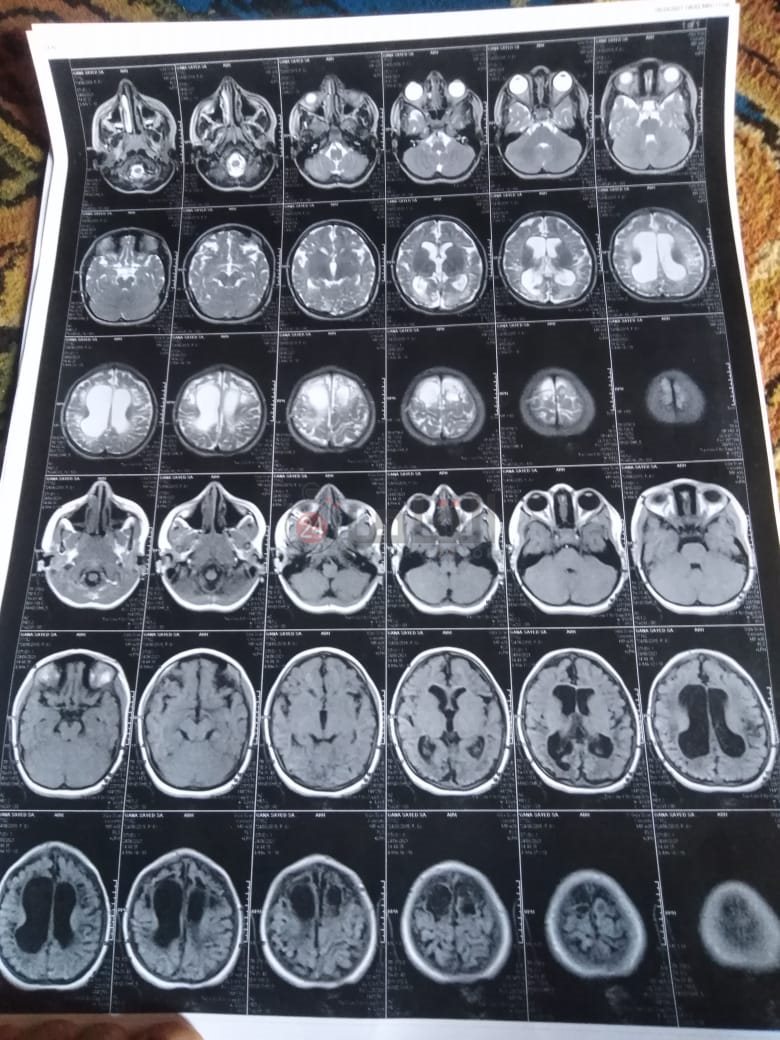

من جانبه، قال صلاح سيد، والد الطفلة جنى صلاح، إن ابنته تعاني من ضمور في المخ منذ ولادتها، نتيجة خطأ طبي، أدى إلى نقص كبير في الأكسجين لديها.

وتابع: "مكنتش بتتحرك خالص، وجسمها طري، روحت كشفت عليها، وعملت أشعة وتحاليل كتير، أتأكدنا إصابتها بضمور في المخ"، مضيفًا:" مش بتعرف تأكل احنا اللي بنأكلها، هي عقلها كويس لكن مش بتتحرك ولا تتكلم".